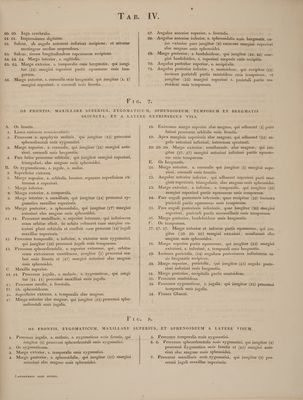

Icones anatomicae / [Conrad Johann Martin Langenbeck].

- Konrad Johann Martin Langenbeck

- Date:

- 1826-1841]

Credit: Icones anatomicae / [Conrad Johann Martin Langenbeck]. Source: Wellcome Collection.